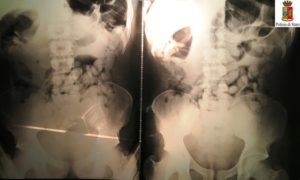

La perquisizione personale aveva avuto esito negativo, ma gli investigatori, ritenendo che potesse trattarsi di due corrieri della droga, li avevano condotti presso l’Ospedale di Susa per accertamenti; al termine degli stessi, le lastre avevano mostrato all’interno della cavità gastrica la presenza di numerosissimi ovuli. Durante la permanenza presso il carcere “Lorusso e Cotugno” in cui sono stati tradotti dopo l’arresto per violazione della Legge sugli stupefacenti, il cittadino maliano ha evacuato 109 ovuli di cocaina, per un peso complessivo di 1246 grammi; il cittadino nigeriano ne ha espulsi 72, per un peso complessivo di 790 grammi.